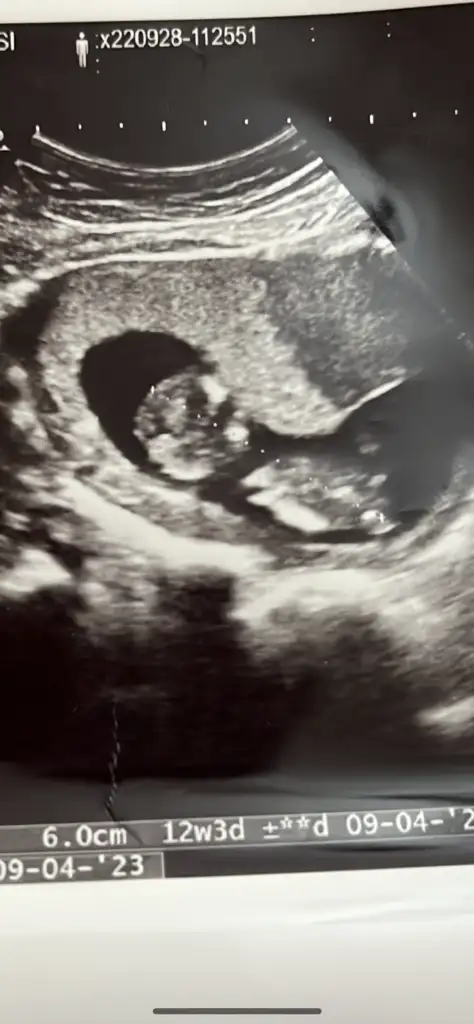

Bugün 12+1 hala bir şey söylemedi doktorum.

12+1 oldum bugün bir tahmin yapmadı doktorum.